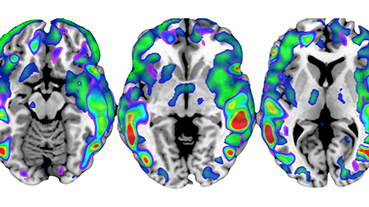

Innovative technologies and alternatives to traditional treatments are transforming the diagnosis and management of neurological conditions. In 2025, NewYork-Presbyterian physicians and surgeons from Columbia and Weill Cornell Medicine used sonication and convection-enhanced delivery to penetrate the blood-brain barrier, validated an adjunctive treatment for subdural hematoma, broadened access to spine surgery, advanced experimental therapies for neurodegenerative diseases, and more. Our specialists have been steadfast in reshaping the fields of neurology and neurosurgery in the pursuit of better patient outcomes and enhanced quality of care.

From cutting-edge research to compassionate patient practice, neurologists and neurosurgeons from Columbia and Weill Cornell Medicine are at the forefront of developing and applying the most advanced approaches to treat debilitating conditions affecting the brain and spine. With a broad range of focus on neurodegenerative and neurovascular disorders to malignant tumors, our innovative and advanced care is leading to new treatment options and enabling patients to achieve the best possible outcomes.